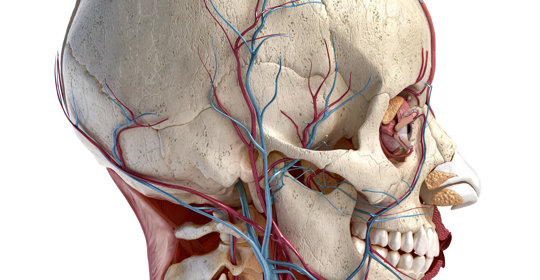

流涎:顏面神經傷害、特發性顏面神經麻痺、腦血管病

口角下垂:中樞性顏面神經麻痺、中風、嘴歪

口唇麻木感刺痛:與三叉神經痛有關,就醫及時